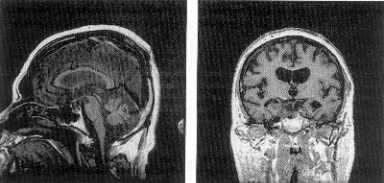

The book has a number of color plates. These are a marvel to look at. Some of these color plates have been scanned at somewhat lower resolution and have been put in a slider viewer here (above and to the right). This is an interactive slide viewer. Readers may want to click on specific buttons to see various color plates. Please click here to go to the Interactive Sliderviewer.